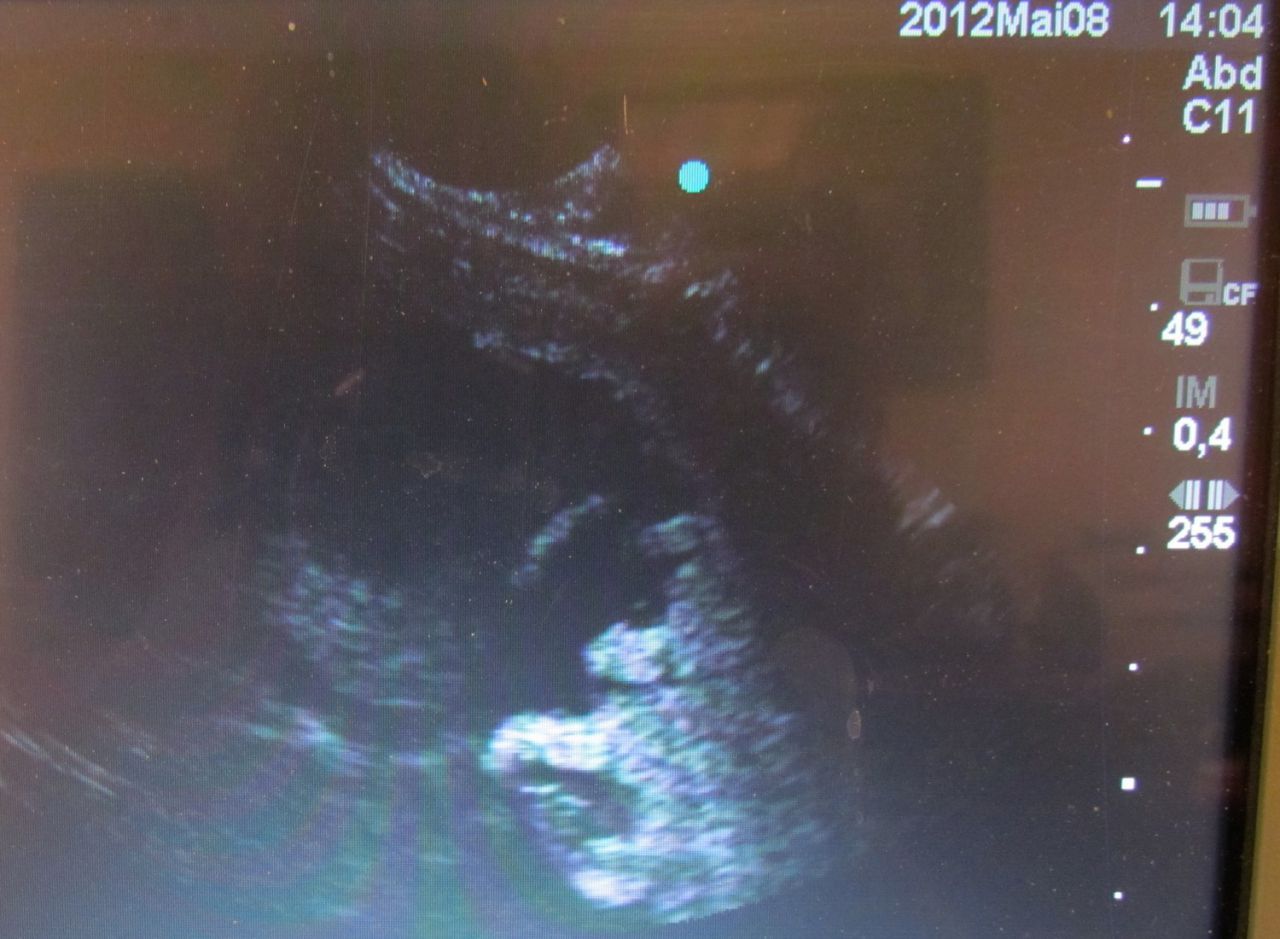

| Dire merci | à votre avis, mâle ou femelle? ![]() ![]() |

| Dire merci | J suis nulle avec ces sondes là! Mais bizarre qu'il n y ait pas de "gris" autour... |

Par al : le 11/05/12 à 09:05:35

| Dire merci | tu veux parler de tout ce fouilli? (qu'on voit en balayant un poil, c'est presque le même endroit en fait) |

Par al : le 11/05/12 à 09:05:45